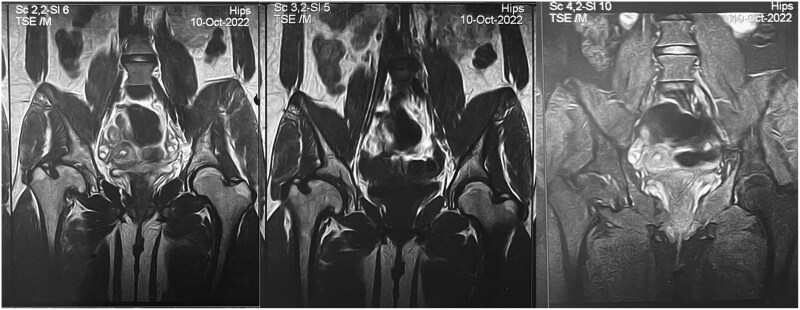

糖原储存病III型(GSD III),或Cori病,是一种罕见的常染色体隐性遗传病,由脱分枝酶缺乏引起,导致糖原异常积累。临床特征包括肝肿大、低血糖、肌病和心肌病。无血管坏死(AVN)是由于血液供应不足导致的骨组织死亡,是GSD III的一种罕见但严重的并发症。本报告讨论了一名已知诊断为GSD III的19岁女性,她发展为AVN,表现为慢性右髋关节疼痛,肌肉无力和低血糖发作。影像学检查解决了诊断难题。治疗包括调整饮食以稳定血糖、对症治疗、使用降脂药物和骨质疏松治疗以解决骨骼并发症。本病例强调了多学科护理、定期监测和个体化管理对于解决罕见并发症和改善GSD III期预后的重要性。

Glycogen storage disease type III (GSD III), or Cori disease, is a rare autosomal recessive disorder caused by a debranching enzyme deficiency, leading to abnormal glycogen accumulation. Clinical features include hepatomegaly, hypoglycemia, myopathy, and cardiomyopathy. Avascular necrosis (AVN), the death of bone tissue due to poor blood supply, is an uncommon but severe complication of GSD III. This report discusses a 19-year-old female with a known diagnosis of GSD III who developed AVN, presenting with chronic right hip pain, muscle weakness, and hypoglycemic seizures. Diagnostic challenges were resolved using imaging studies. Management included dietary adjustments to stabilize blood glucose, symptomatic treatment, lipid-lowering agents, and osteoporosis therapy to address skeletal complications. This case highlights the importance of multidisciplinary care, regular monitoring, and individualized management to address rare complications and improve outcomes in GSD III.